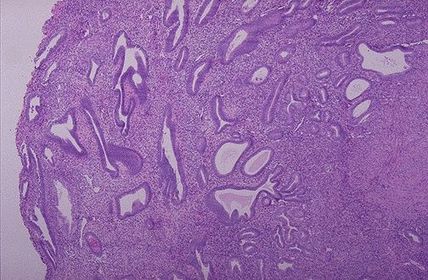

where am I from the universe o.O?! TISSUE TYPE: see glands and stroma... UTERUS PATHOLOGY: hyperplastic glands with different sizes and shapes DIAGNOSIS: endometrial hyperplasia KEY: FIND THE SWISS CHEESE XD..